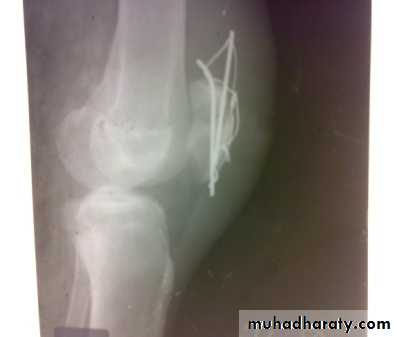

Internal fixation/pop cylinder

For the fracture caused by indirect force:

. Operation is essential. Through a longitudinal incision the fracture is exposed and the patella repaired by the tension-band principle . The tears in the extensor expansions are then repaired.